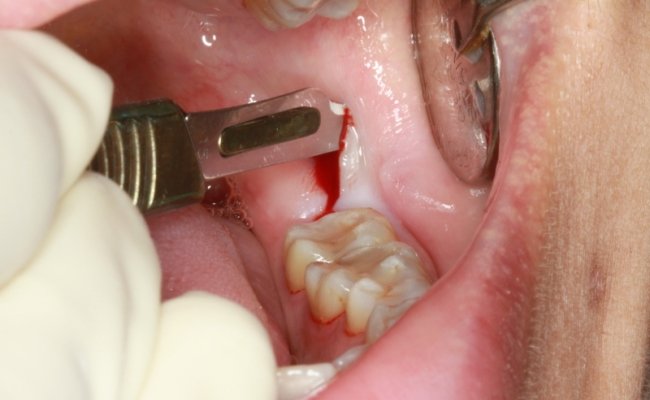

Tiểu phẫu răng khôn

3. Khi nào nên nhổ răng khôn?

Lý do cần nhổ răng khôn là bởi răng khôn thường mọc ở các vị trí không thuận lợi, hoặc khi xương hàm đã hết chỗ mà răng khôn lại nằm quá sâu trong hàm. Việc này sẽ khiến khó vệ sinh, tạo môi trường thuận lợi cho vi khuẩn phát triển, sinh sôi và tăng nguy cơ viêm nướu, sâu răng.

- Cần nhổ răng khôn khi răng khôn mọc gây các biến chứng đau, u nang, nhiễm trùng lặp đi lặp lại, ảnh hưởng đến các răng lân cận.